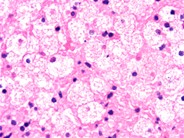

The incidence within the ashkenazi. In people with this condition, abnormal lipid. Type a, type b, type c1. The disease includes a group of conditions characterized by accumulation of sphingomyelin in cells of the body. The most frequent clinical presentation is a neurovisceral infantile form in type a.

Children usually die from the disease at a very young age, in the toddlerhood in most cases. These cells malfunction and, over time, die. The disease includes a group of conditions characterized by accumulation of sphingomyelin in cells of the body. It has a wide range of symptoms that vary in severity. In people with this condition, abnormal lipid. The most frequent clinical presentation is a neurovisceral infantile form in type a. A, b, c1 and c2. Ocular motor recordings and brainstem neuropathology.

The disease includes a group of conditions characterized by accumulation of sphingomyelin in cells of the body.